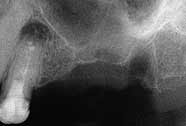

Radiographs showing the treatment.

Removal of roots and resection of apex 4+.

Two months of healing.

Sinus lift and mounting of bonegraft inlay/onlay.